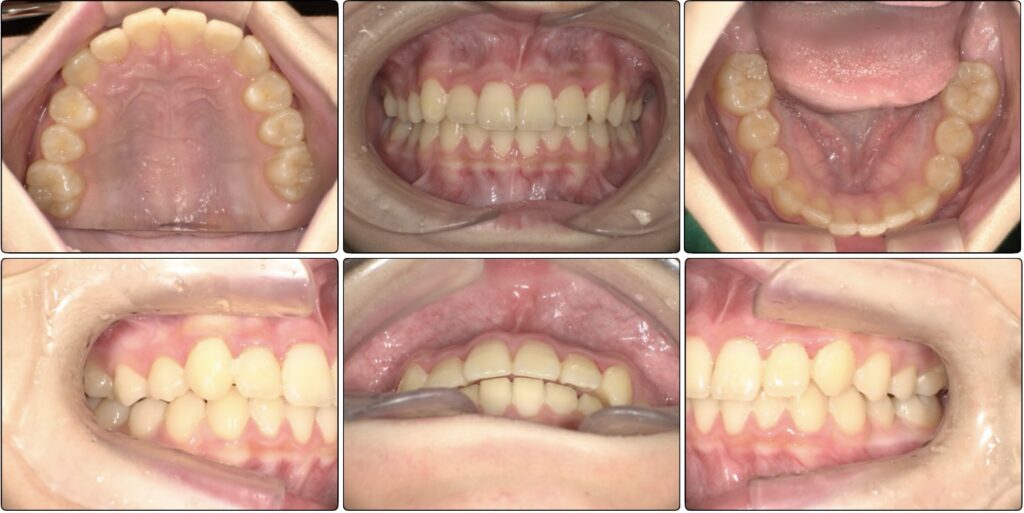

治療前 / 現在

治療開始時

現在

装置セットから外して数ヶ月後の写真です。

もう3番目の歯は綺麗に並ぶので全ての装置を外しました。

(アクティビティー終了しているため、マウスピースのに使用しています)